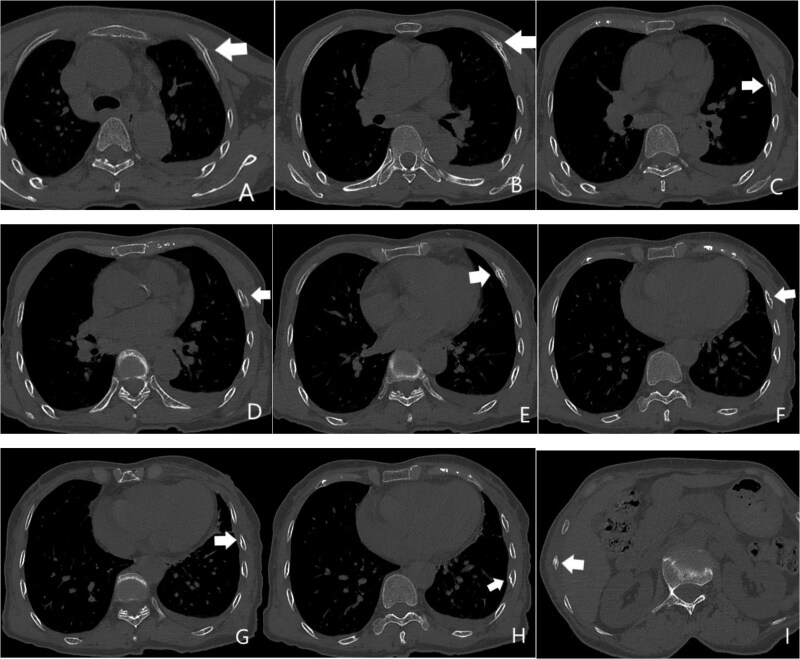

Trauma in victims of abuse often exists in various ways, and the characters usually manifest as non-fatal injuries, repetitive occurrence, and the injured parts are relatively hidden. Forensic experts are optimally positioned to raise suspicion for abuse when comprehensively considering a forensic investigation, reviewing imaging, and other multiple factors of geriatric injury victims. However, few experts received formal or informal training in abuse identification. In this article, we discussed two cases of suspected victims of abuse with rib fractures and attempted to determine the location, timing, and directionality of these injuries to raise the index of suspicion for abuse. We present two cases to characterize the radiographic changes of rib fractures in various stages of healing and radiographic findings in elder abuse events. To improve the accuracy of the imaging diagnosis, we collected a series of computed tomography images of rib fractures and compared all computed tomography images of these two victims with these images. We found that the victims presented with repeated rib fractures and with different stages of healing. We strongly suspect these were abuse cases due to the radiographic findings and clinical recordings demonstrated by these cases. We aim to raise awareness of abuse in radiology and forensic medicine to help these victims and reduce such incidents.